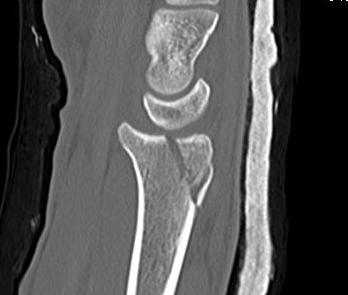

Distal Radius Fracture Articular Step Coronal CTDistal Radius Fracture Articular Step Sagittal CT

Articular incongruency > 2 mm